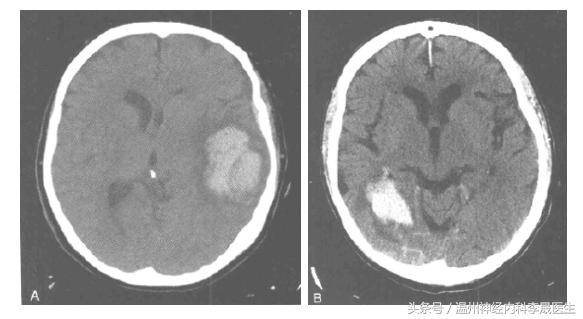

壳核出血

壳核出血(大)

壳核出血(A)小壳核范围内的出血,(B)侵犯了内囊,(C)血肿压迫侧脑室